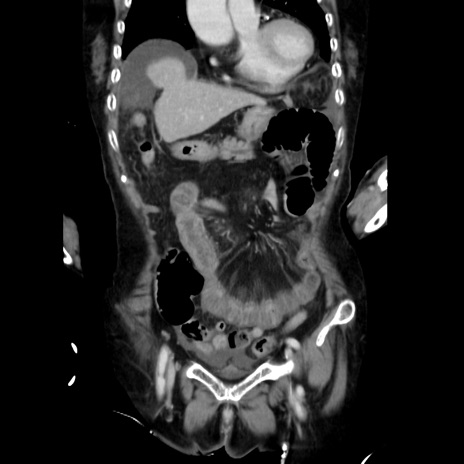

症例40(冠状断像)

【症例】90歳代女性

【主訴】腹痛・嘔吐

【現病歴】 食欲低下、嘔吐があり昨日他院受診。肺炎と診断され入院となる。入院後より腹部全体に圧痛あり。胃管留置され経過みていたが、症状持続するため、

当院転院となる。

【既往歴】胸椎圧迫骨折、胆石症

【身体所見】腹部:中央に激痛あり、圧痛あり、反跳痛不明

【データ】WBC 17100、CRP 18.82

冠状断像